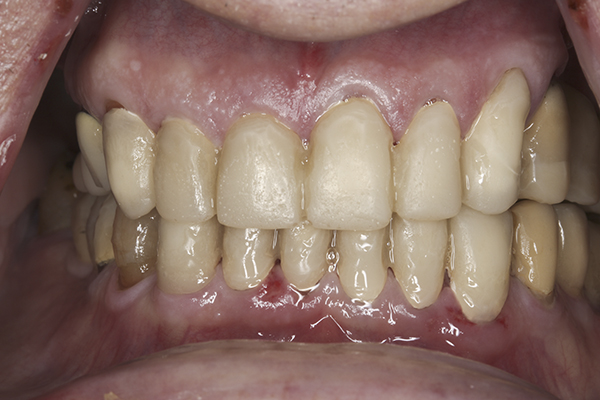

(10.) Preoperative anterior, closed view. Note the end-to-end occlusion of the anterior teeth and the wear on the incisors and centrals resulting in no anterior or canine guidance.

Figure 10